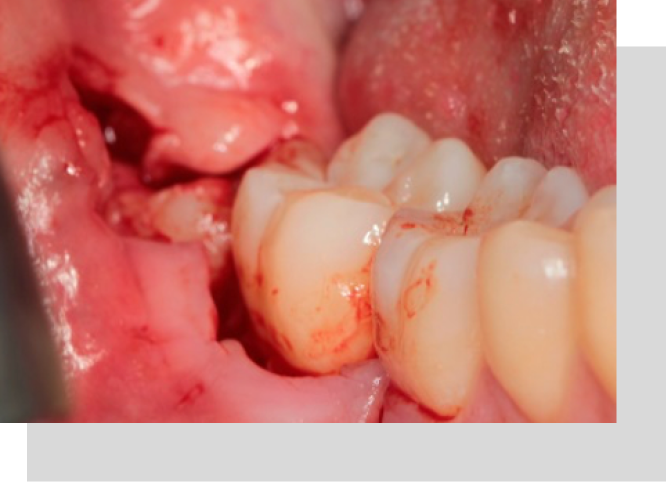

Extracción De Dientes Complejos, Ectópicos O En Mala Posición

Es la extracción de dientes en mala posición, o que se encuentran en los maxilares pudiendo causar dolor, quistes, entre otras condiciones.

Tratamiento De Quistes O Tumores De Los Maxilares

Se evaluará caso a caso, si el paciente tiene alguna inflamación que no disminuye con el tiempo, dolorosa o no dolorosa, tiene algún tipo de secreción de líquido o alguna otra sustancia, debes consultar.